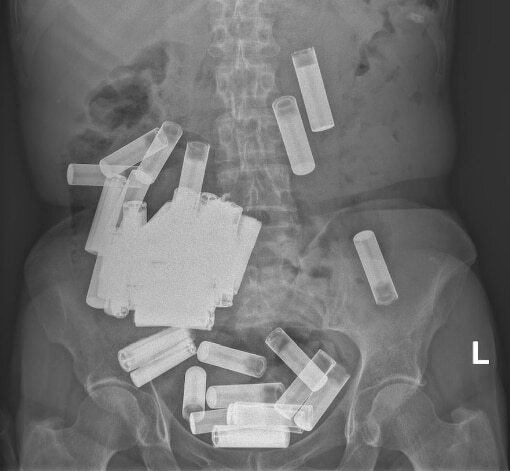

A씨는 복통을 호소하다 아일랜드 더블린의 한 병원에 갔다. 엑스레이 촬영 결과 A씨의 뱃속에 수십개의 건전지가 있는 것이 확인됐다.

의료진은 A씨가 장폐색이나 위장 천공 등의 징후를 보이지 않아 비수술 치료를 권했다. 이후 A씨는 일주일 동안 AA건전지 5개를 대변으로 배출해냈다. 그러나 나머지 건전지는 위장에 끼어 3주가 되도록 배출되지 않았다.

결국 A씨가 복통과 식욕부진 등을 호소하기 시작하자 의료진은 개복수술을 통해 남은 건전지 46개를 꺼냈다. 결장에 있던 4개의 건전지는 직장을 통해 항문으로 제거했다. 당시 A씨의 위는 건전지 무게 때문에 치골까지 늘어난 것으로 전해졌다. 건전지 제거 이후 A씨의 상태는 빠르게 회복됐다고 한다.